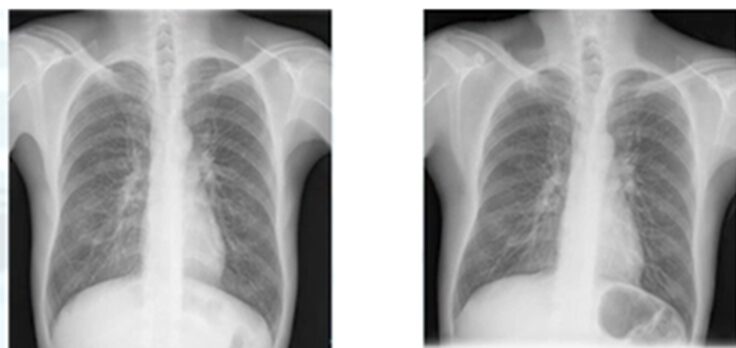

左が1年前、右が今年のレントゲン写真です。

所見としては、右肺尖部、鎖骨下に結節影が出現していることが分かります。

鎖骨や肋骨など、影が多い場所で異常を見つけるコツとしては

・骨からはみ出しているものに注意する

・過去の写真と比較する

このような所見が挙げられます。その後CT検査に進んでいます。